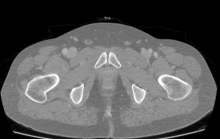

A 53-year-old man was admitted with a two-month history of anterior myocardial infarction, congestive heart failure, and a New York Heart Association III classification. Echocardiography showed severe mitral insufficiency (Carpentier I, IIIb), left ventricle aneurysm, and left ventricle ejection fraction (EF) 35%. An angiogram showed severe triple vessel disease.

The authors performed coronary artery bypass grafting combined with mitral valve repair and left ventricle aneurysm repair using a minimally invasive approach through the left anterior thoracotomy in the fourth intercostal space. The left internal mammary artery and saphenous vein were harvested. The authors used peripheral cannulation (femoral) for cardiopulmonary bypass (CPB). The aorta was cross-clamped and cold blood cardioplegia was administered every 15-20 minutes. The following distal anastomoses were performed: vein to PDA, vein to OM, and left internal mammary artery to left anterior descending artery (LAD). Then, a 5 cm incision was made in the left ventricle anterior wall parallel to the LAD through the aneurysmal tissues. The mitral valve was exposed and an Alfieri stitch was done between the A2 - P2 segments of the mitral valve leaflets. Then, a left ventricle repair using two layers of endoventricular suture lines with polypropylene 3-0 was performed. The volume of the left ventricle was reduced and the shape was restored. Proximal anastomoses to the aorta with two vein grafts were completed using a side-biting aortic clamp. Cardiopulmonary bypass was weaned and the wound was closed.